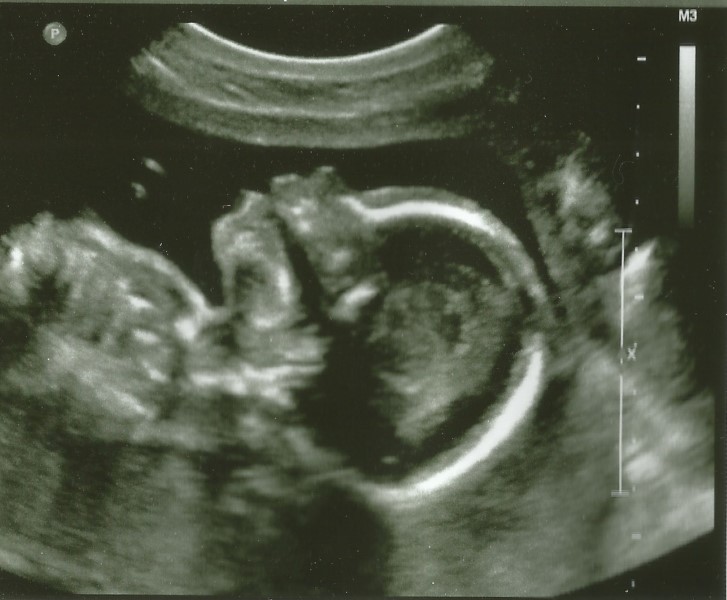

Does Placenta Previa Require Bed Rest . Placenta previa is a relatively rare pregnancy complication in which the placenta implants low in the uterus and covers part or all of the cervix. Here's what you need to know about bed rest and pelvic rest during pregnancy, from side effects to making the best of it. Bleeding due to placenta previa (the placenta covers part or all of your cervix) or placental abruption (the placenta. Carusi and feldbaum agree that people with placenta previa need to go on what they call “pelvic rest,” meaning nothing should enter your vagina (yep, that means no intercourse). Placenta previa occurs when the placenta—the organ that provides nutrients to a growing fetus—becomes attached to the lowest part of the uterus, covering part or all of the cervix. The initial diagnosis may be done with. Placenta previa is a problem of pregnancy in which the placenta grows in the lowest part of the womb (uterus) and covers all or part of the opening to the cervix.

Placenta previa is a problem of pregnancy in which the placenta grows in the lowest part of the womb (uterus) and covers all or part of the opening to the cervix. Bleeding due to placenta previa (the placenta covers part or all of your cervix) or placental abruption (the placenta. The initial diagnosis may be done with. Here's what you need to know about bed rest and pelvic rest during pregnancy, from side effects to making the best of it. Placenta previa is a relatively rare pregnancy complication in which the placenta implants low in the uterus and covers part or all of the cervix. Carusi and feldbaum agree that people with placenta previa need to go on what they call “pelvic rest,” meaning nothing should enter your vagina (yep, that means no intercourse). Placenta previa occurs when the placenta—the organ that provides nutrients to a growing fetus—becomes attached to the lowest part of the uterus, covering part or all of the cervix.